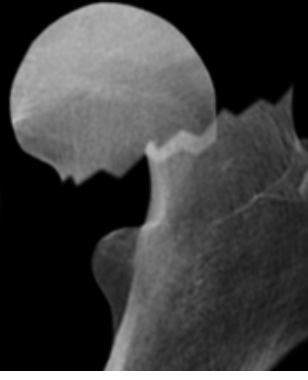

What type of Garden classification is this? [1]

A

IV - Complete - totally displaced